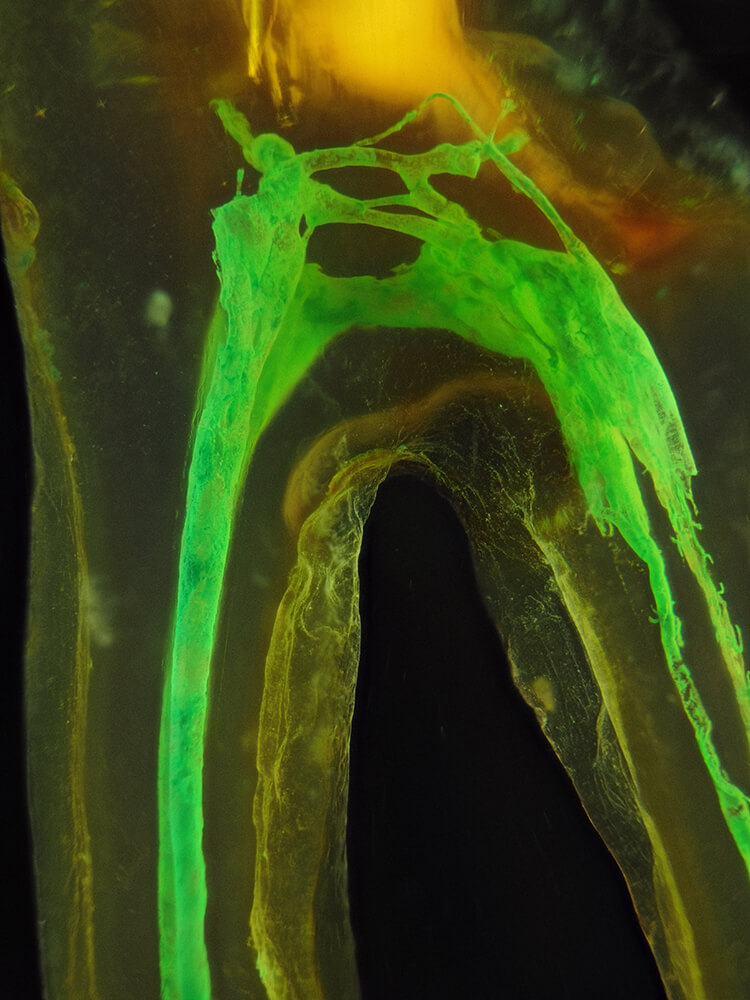

Das Verfahren, Zähne in durchsichtige Präparate zu überführen ist schon über 100 Jahre alt. Aber erst durch die Weiterentwicklung der alten Technik und die Kombination mit moderner Fotografie sowie der Entwicklung eines geeigneten Gefäßes zur Fotografie ist es meinem Vater Dr. Holm Reuver gelungen, einzigartige Bilder vom Inneren der Zähne aufzunehmen.

Die Bilder sind in verschiedenen Größen wählbar und auch als POPART-Variante erhältlich. Sie sind hervorragend geeignet für die Beratung von Patienten vor endodontischen Behandlungen, aber auch ein beliebter Eyecatcher im Wartezimmer. Außerdem haben die Bilder einen bedeutenden Stellenwert für die Erforschung der Pulpatopografie und für die Lehre im Bereich der Endodontie.

CLEARINGSERVICE bietet Ihnen die Möglichkeit, wurzelgefüllte Zähne mit der Technik des Transparentmachens untersuchen zu lassen. Das geht sehr einfach: Sie schicken uns den zu untersuchenden Zahn, dieser wird dann in ein transparentes Präparat überführt und mit hochwertiger Makrofotografie ausgewertet. Anschließend bekommen Sie die angefertigten Präparate zusammen mit der Fotodokumentation zugeschickt.